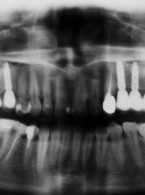

Dekoronacja

jako postępowanie zalecane w leczeniu pacjentów z postępującą pourazową infrapozycją zębów siecznych szczęki